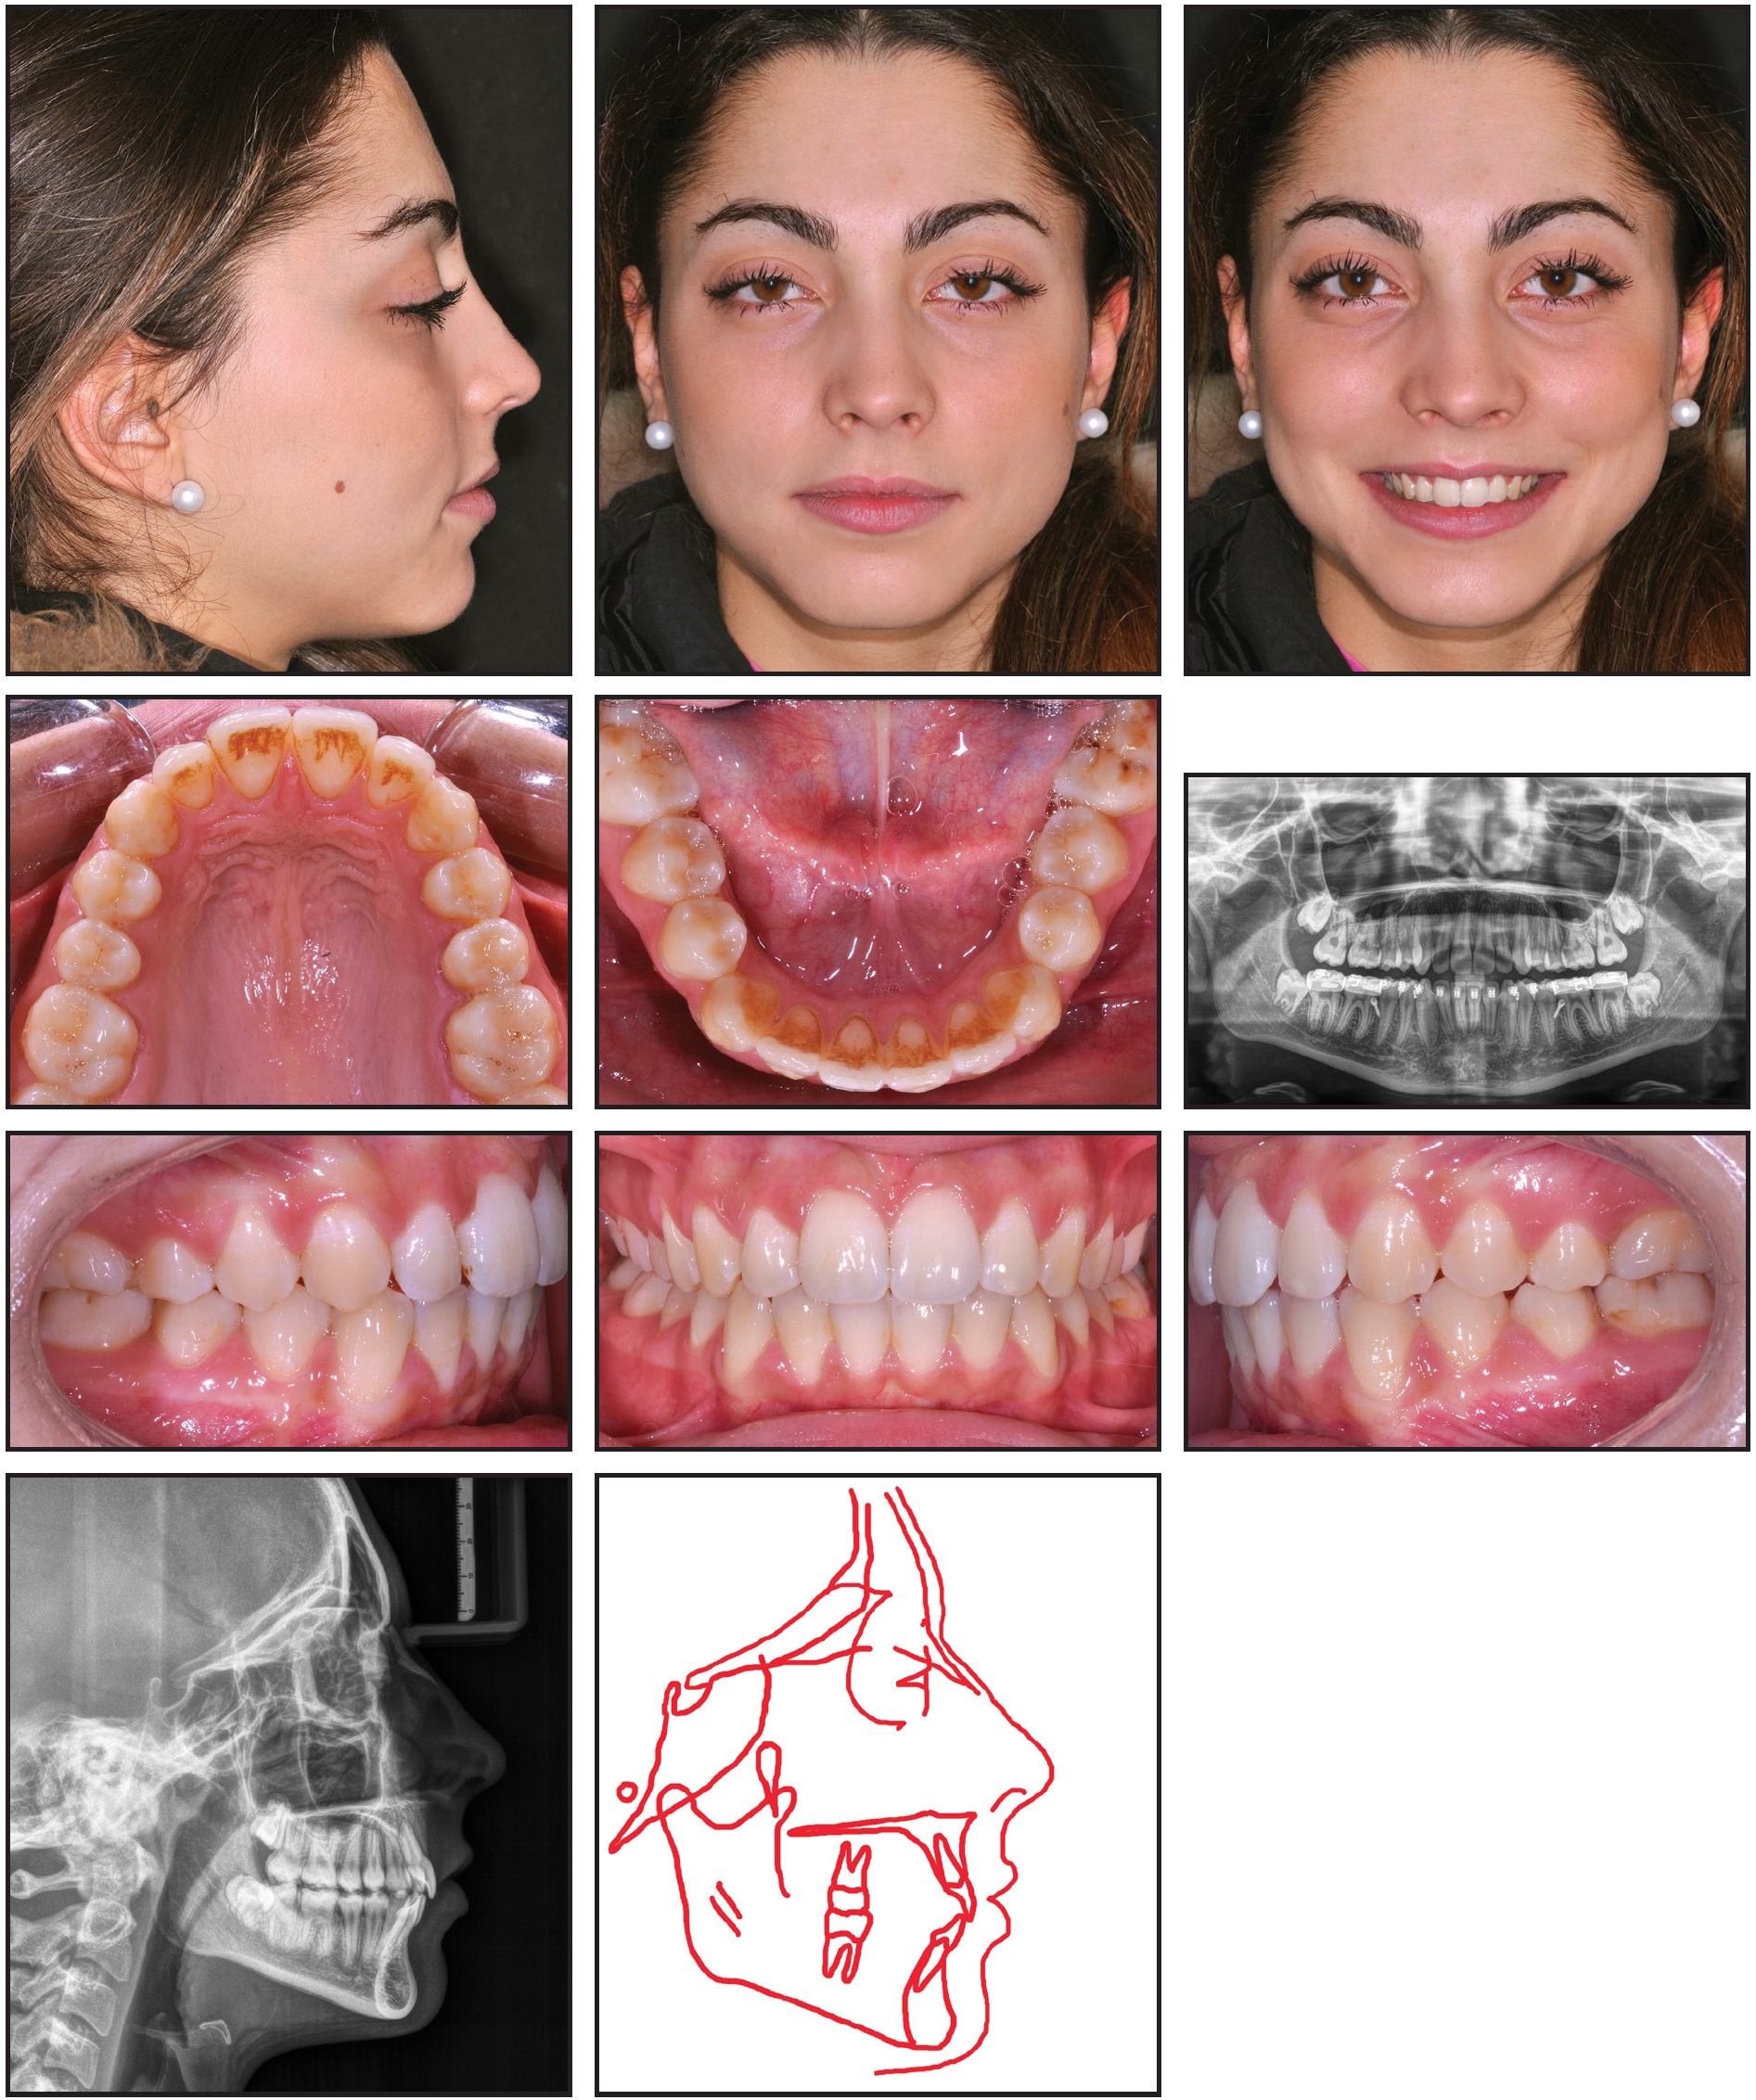

A 12-year-old female was referred by her dentist for orthodontic correction of protrusive maxillary teeth. Clinical examination showed bilateral Class II molar and canine relationships, with a 1mm discrepancy between the upper and lower dental midlines, a convex profile, and incompetent lips (Fig. 1).

Fig. 1 12-year-old female patient with convex profile; retrusive mandible; anterior crowding; and Class II, division 1 malocclusion before treatment.

The patient exhibited a crossbite between the upper and lower left first premolars. The maxillary arch was constricted, with anterior crowding; the mandibular arch also had mild anterior crowding.

The panoramic radiograph showed the presence of all permanent teeth. Cephalometric analysis indicated a skeletal Class II malocclusion (Table 1).